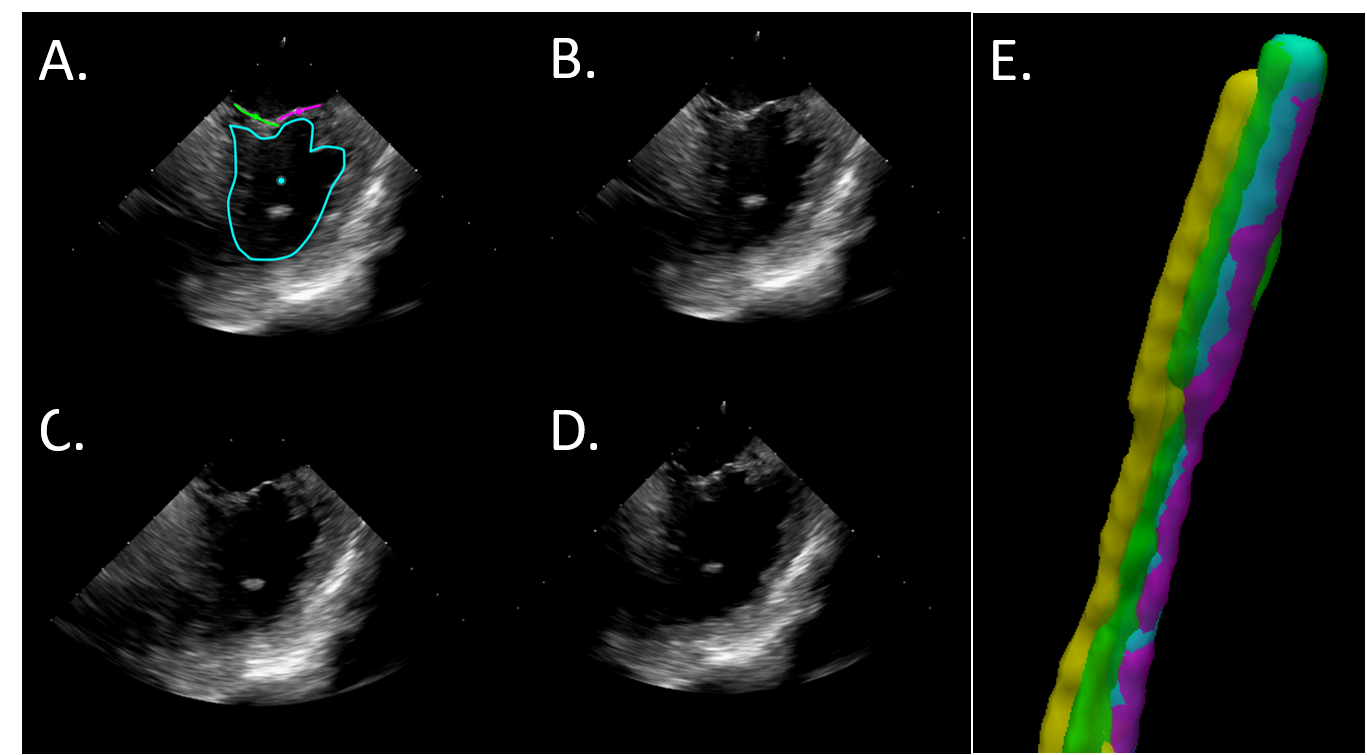

Refer to caption

Figure 6: Diagram of seven automated catheter returns to a single image-target. The black catheter, marked by *, represents the spatial average of the other seven. In this scenario, the purple catheter, marked by x, was designated as the reference catheter to which comparisons are made as it is the geometric median. The observed spread relative to the purple catheter represents the error associated with the automated view recovery as reported in this study.

Validation metrics:  For this study, we compare catheter tip location across multiple robotic positioning events to an image target as the primary spatial validation approach. For any catheter positioning to an image target, the robotic motors will theoretically return to an identical final state, assuming no slippage and consistent backlash. As we have created an open-loop system, when the robot executes movement along a path it is unaware of any influences external to the controller which may affect its final positioning. As such, we assume that any error in the positioning of the catheter tip are due to those external influences (e.g. catheter-robot mechanics, intravenous catheter interactions, cardiac and respiratory motion, etc). These measurements, when taken relative to a reference catheter position, represent the distribution of uncertainty in robotic catheter positioning resulting from these external sources of error. Because of this, each experimental robotic positioning of the catheter to an image target can be considered a sampling of that uncertainty (Figure 6). Therefore, we have elected to use the geometric median catheter (i.e. the catheter which presented nearest the centroid of the sampled distribution) as the reference catheter for each imaging target when evaluating the view recovery process.

To measure in vivo, 3D models of the ground-truth observance of each ICE catheter were generated following an intensity-based threshold segmentation of intra-procedural DCT images (voxel spacing 0.498 mm) using ITK-SNAP  [50]. Co-registration between DCT images were not necessary as no bulk subject motion was observed between scans. Next, the ICE catheter tip was manually labeled within each model and the centroid taken to define the discrete tip location for a given robotic positioning event. A curve was then fit to each catheter, constrained to terminate at the predefined catheter tip, by fitting a low-order polynomial. This process provided a discrete spatial representation of the catheter tip and body. Finally, catheter tip position error was calculated as the Euclidean distance between each catheter tip location and the respective reference catheter tip location for each imaging target.

Robotic catheter positioning was further evaluated by measuring the similarity of acquired ultrasound images between each experimental acquisition and the reference acquisition. Ultrasound image clips encompassing multiple heart cycles were acquired following each robotic positioning event. Image sequences were manually synchronized in time based on visible anatomy (e.g. valve leaflet position; from the first frame of the target valve being open to the last frame before re-opening in the next cycle) and trimmed to encompass exactly one heartbeat. As before, image sequences from the geometric median catheter were selected as the reference images for comparison. Ultrasound images for each series of target view were then compared, in the labeled corresponding frames, to the reference images by computing the image cross-correlation. In-image regions of interest (ROI) were also manually labeled for each image series (Figures 8(A) and 9(A,C)). ROI centroids from each image acquisition were measured to corresponding ROI centroids in the reference images by Euclidean distance.

IV-B2 Phantom validation of automated view recovery

Unique initial catheter tip positions were manipulated to within the beating heart phantom by joystick input to the robotic controller and saved (i.e. the joystick input maps to the standard catheter control knobs, these digital inputs are then translated to the robotic motors to result in catheter manipulation). For each target, the robotic control state was then added to the library of views for later automatic return via topological path planning. The controller was then tasked with cycling the ICE catheter tip between each target position in series a total of 16 times. Accuracy of the robotic controller was measured by an EM sensor attached at the catheter tip. The set of target positions encompassed manipulation of all 4 DOF of catheter motion. Under these conditions, the robotic controller maneuvered the catheter tip to the target position with an average position error of 0.67±0.79mmplus-or-minus0.670.79𝑚𝑚0.67\pm 0.79~{}mm and rotational error of 0.37±0.19plus-or-minussuperscript0.37superscript0.190.37^{\circ}\pm 0.19^{\circ}.